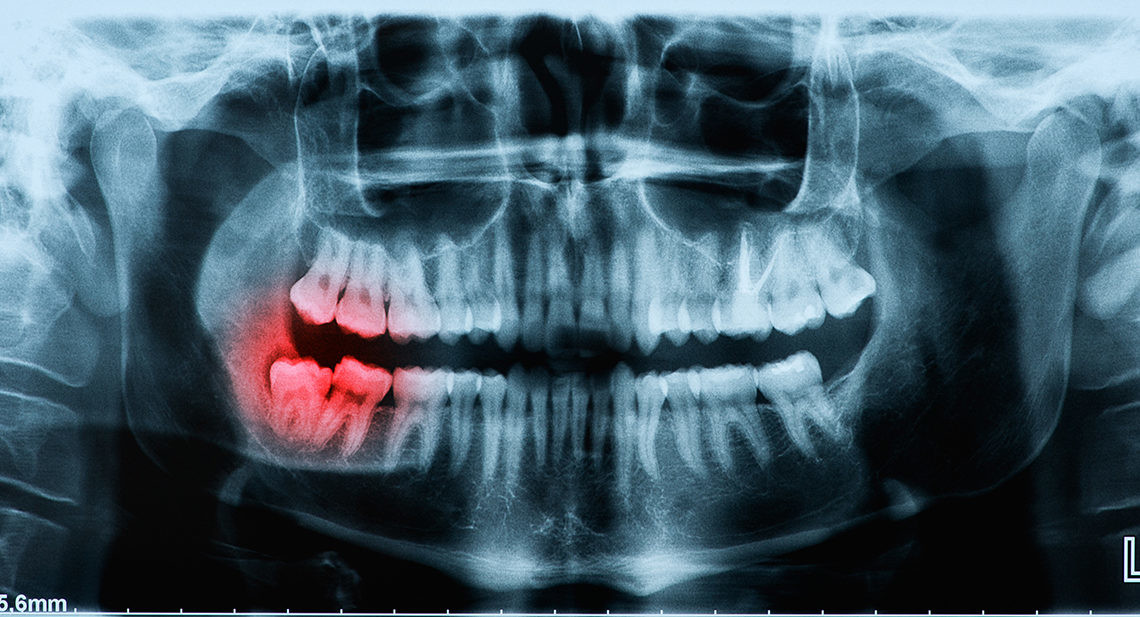

Broken Wisdom Tooth – Is It Considered An Emergency?

Wisdom teeth are usually the last adult teeth to come through and tend to erupt in the later teens or early twenties. Known as the third molars, they do not always come through the gums at all, and if they do, sometimes they may not be straight.

In these cases, there may be an increased risk of infection. Gaps allow debris to gather and bacteria to grow, which raises the risk of gum disease and tooth decay. Some experts recommend the early removal of wisdom teeth to avoid such occurrences, while others believe it is best to leave them alone if possible.

However, one situation where your dentist is very likely to recommend removal is if a wisdom tooth is broken. While it is possible to retain the broken tooth, to avoid further complications, it is best to get the tooth removed completely.

Why Do Wisdom Teeth Break?

As wisdom teeth are the last to come through, there may be limited space in your mouth. As they try to erupt through your gum, another tooth may already be occupying the same spot. Your wisdom tooth may come through at an unnatural angle, or even crack as it forces its way out.

Wisdom teeth may be more likely to break than your other teeth if they have not erupted correctly. You may find it more challenging to use those teeth to chew, and there is a greater chance of decay if it is harder to clean thoroughly around that area.

As with any other tooth, your wisdom teeth are susceptible to blunt force trauma, such as an impact on your jaw, or biting into something hard. If your teeth crack, or fragments of your wisdom tooth break off, this is likely to cause discomfort.

Risks from Having a Broken Wisdom Tooth

Bacteria can thrive in gaps where bits of the tooth broke. A gap in a wisdom tooth is a hospitable environment for an infection and a weak point in the tooth.

Additionally, a broken or cracked wisdom tooth puts the entire tooth’s health at risk. Bacteria can invade the tooth and infect the dental pulp. In those cases, the tooth must either be extracted or given a root canal treatment. In most cases, it’s better just to remove the tooth.

It is essential to see your dentist quickly if you have a broken wisdom tooth. Your dentist will carry out an assessment and tell you if you should have a wisdom tooth extraction.

Although it is possible to fill a broken tooth, or repair it using a crown, you will want to consider removing your wisdom tooth. Wisdom teeth usually do not bring any real benefits to your mouth, but they can increase the chances of breakages and infections.

Wisdom Teeth Removal

If you need to have your wisdom teeth removed, your dentist can perform the procedure in just one visit. Depending on how your tooth has erupted through the gums and sits in the jawbone, you may need a simple or complex extraction.

In a simple extraction, your dentist numbs the area around the tooth and using a rocking motion, loosens the tooth from its socket. In a complex extraction, you may require general anesthesia or conscious sedation, especially if you are an anxious patient.

Your dentist makes an incision in the gum line and breaks the tooth into sections, removing the pieces. After the extraction, your dentist places a piece of gauze over the site to stem the bleeding and may use sutures. Bring a chaperon to drive you home, as the sedation’s effects can last in the body for a few hours after your procedure.